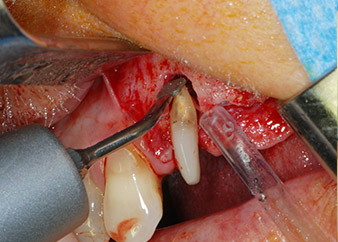

Un mes después, en el día de la intervención, el dolor y la inflamación se habían reducido al mínimo en la pieza 24, pero seguía habiendo una movilidad de clase II de Miller. Después de la apertura de los colgajos y de la limpieza del tejido infectado periapical y perirradicular, la extensión del defecto óseo quedó evidente (figuras 2 y 3).

la raíz bucal de la pieza 24 mostraba una pérdida total del hueso y de la fijación

Fig. 2 y 3: Después de abrir los colgajos, un mes después de realizar la revisión endodóntica y de iniciar la terapia periodontal en toda la boca, la raíz bucal de la pieza 24 mostraba una pérdida total del hueso y de la fijación.